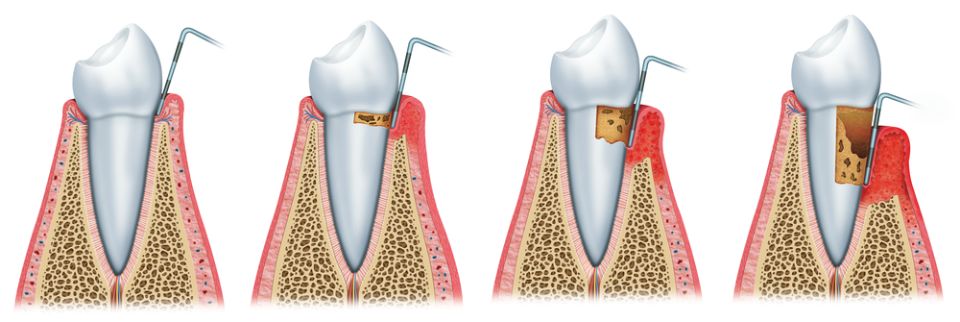

La Periodòncia és lespecialitat odontològica dedicada a lestudi del periodont o lestructura de suport de les dents. Engloba la prevenció, el diagnòstic i el tractament de les malalties que afecten aquests teixits que envolten i subjecten la dent a l'os (geniva, ciment radicular, lligament periodontal i os alveolar).

Dins de les malalties periodontals més conegudes trobem:

La gingivitis que cursa amb inflamació i envermelliment de les genives i possible sagnat al raspallat.

La periodontitis clínicament presenta els signes de la gingivitis però també s'acompanya de la pèrdua dels teixits que suporten la dent: el lligament periodontal i l'os alveolar, causant-ne la mobilitat de la dent i futura pèrdua si no es tracta.

Les causes de la periodontitis són la combinació de la presència de bacteris patògens juntament amb els factors genètics (resistència de cada persona a les infeccions). A part, se li sumen altres factors que poden condicionar la seva evolució com: tabaquisme, hàbits higiènics, certs medicaments, la diabetis...

La recessió gingival no és una malaltia pròpiament dita sinó un trastorn morfològic on el retrocés de la geniva marginal pot presentar problemes estètics i molèsties a causa de la sensibilitat produïda per l'exposició dels colls dentals. Les causes més freqüents són per un raspallat incorrecte, per una sobrecàrrega funcional o bé degut a una periodontitis crònica no tractada.

El nostre objectiu principal és la prevenció de l'aparició de la periodontitis i en cas de diagnosticar-se, tractar-la per poder eliminar la inflamació i poder aturar-ne la progressió. Per això, és important que el pacient tingui un bon hàbit d'higiene bucal i assisteixi a les revisions i visites periòdiques del dentista.

De vegades no podem tractar la periodontitis només amb tractament conservador i cal recórrer a tècniques quirúrgiques per aconseguir millors resultats, per exemple amb la cirurgia periodontal.

Hi ha altres tipus d'intervencions quirúrgiques a nivell de les genives i de la mucosa bucal com ara: les gingivectomies/gingivoplàstiques i els allargaments de corona que serveixen per salvar dents compromeses o bé per aconseguir canvis estètics en el somriure. Un altre exemple seria la cirurgia mucogingival utilitzada per cobrir recessions, guanyar volum dels teixits tous periodentals o bé aconseguir una geniva més forta i sana al voltant de dents o implants.